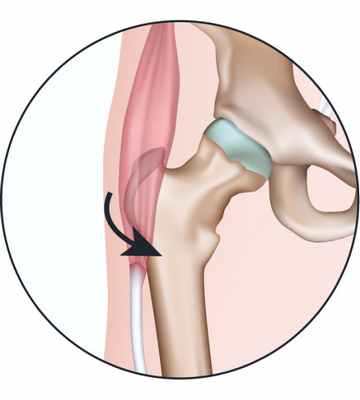

При сгибании ноги в тазобедренном суставе сухожилия сдвигаются и оказываются кпереди от большого вертела. Так как большой вертел слегка выступает, то при движении сухожилий относительно него можно услышать щелчок. Такое состояние может привести к бурситу тазобедренного сустава. Бурсит - это воспаление и утолщение синовиальной сумки: мешка с гладкими стенками, заполненного жидкостью, который обеспечивает беспрепятственное скольжение мышц относительно костей.

Синдром щелкающего бедра может быть вызван сухожилием прямой мышцы бедра, которая проходит по передней поверхности бедра и крепится к тазовой кости. При сгибании бедра сухожилие смещается относительно головки бедренной кости; при выпрямлении нижней конечности сухожилие возвращается в исходное положение. Эти возвратно-поступательные движения сухожилия по поверхности головки бедренной кости и вызывают щелчки.

Причиной «щелкающего бедра» является изменение в мышце, натягивающей широкую фасцию бедра. Обычно эта мышца удерживается над большим вертелом благодаря связи с глубоко лежащими мышцами. При нарушении этой связи мышца начинает скользить на большом вертеле, вызывая характерный щелчок. Ранее причиной «щелкающего бедра» считали якобы происходящие кратковременные подвывихи головки бедренной кости. Но исследования тазобедренного сустава показали, что патологии в суставе нет. Это заболевание наблюдается только у балерин в момент, когда они всеми способами стараются снизить массу тела и похудеть. Это ведет к ослаблению тонуса мышц, в частности, мышцы, натягивающей широкую фасцию бедра.